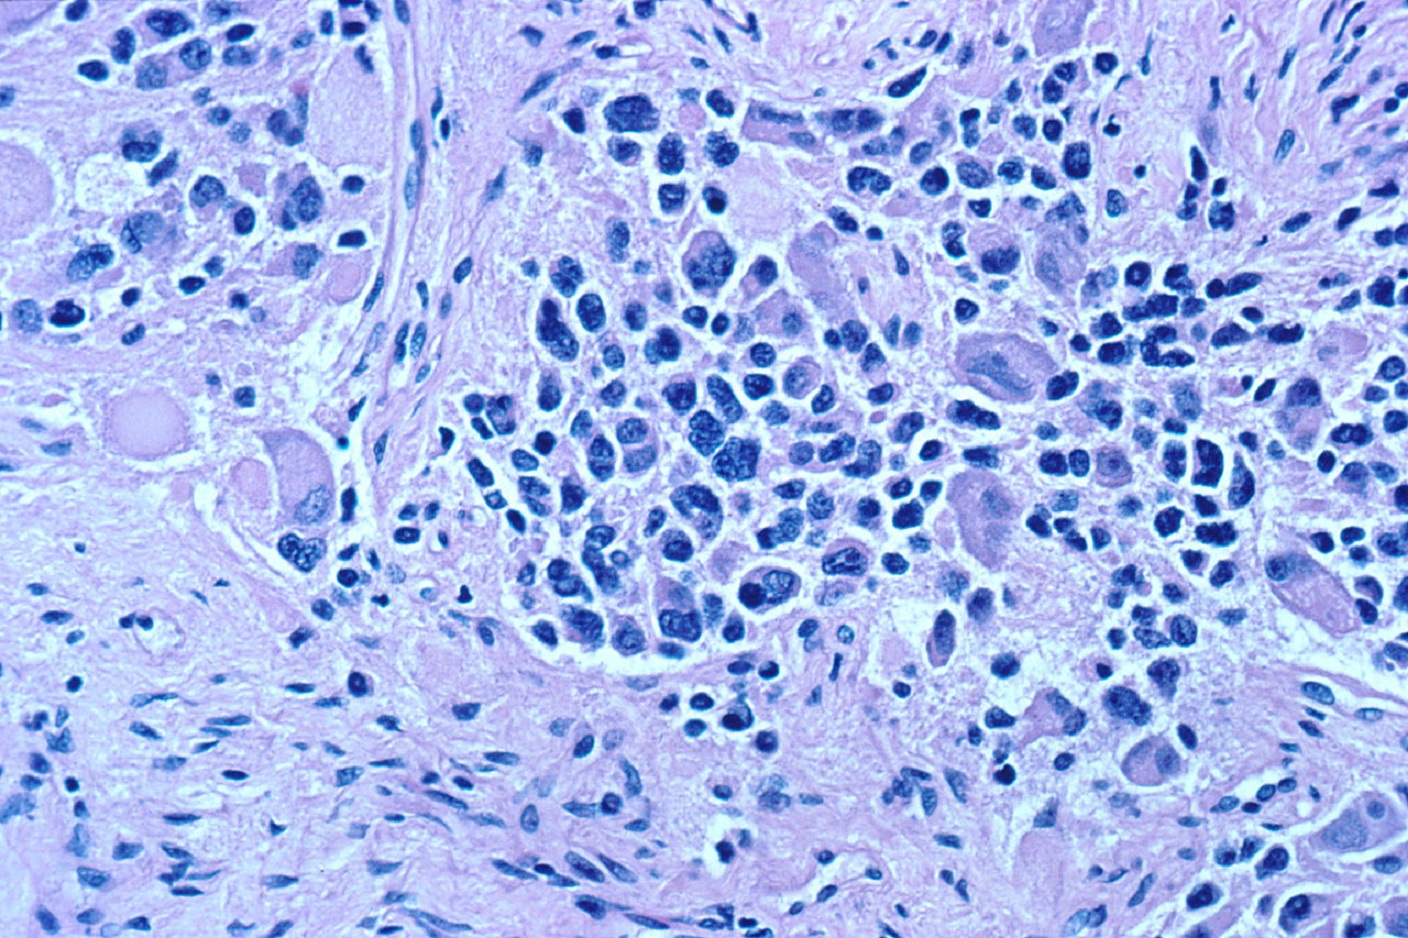

El neuroblastoma es el tumor sólido extracraneal más común en la infancia. Se caracteriza porque comienza en las células nerviosas inmaduras del sistema nervioso simpático. Las fibras de este sistema llegan a casi todos los órganos y sistemas del cuerpo, desde la pupila del ojo hasta ejercer control sobre la motilidad intestinal.

Pues bien, en este tipo de tumores las células cancerígenas que lo conforman contienen una molécula que interrumpe un recurso de energía clave para las células del sistema inmune. Los investigadores explican que, debido a esto, las células inmunitarias no tienen opción de captar energía para ejercer su actividad, por lo que quedan físicamente agotadas para luchar contra la dolencia. Expliquemos un poco en que consiste todo este proceso.

Los investigadores descubrieron que las células del neuroblastoma producen una molécula que descompone la arginina, uno de los aminoácidos esenciales que forman parte de las proteínas y una fuente de energía primordial para las células inmunes ya que estimula la función inmunológica.

Esta molécula, responsable de la descomposición de la arginina, se denomina <i>arginasa</i> y lo que hace es provocar una enorme caída en los niveles de arginina encontrada en el área que rodea al tumor. De tal forma, que tan pronto como las células del sistema inmune se aproximan a las células cancerígenas, la repentina carencia de su principal fuente de energía hace que se vuelvan letárgicas e inefectivas.

Esto permite la formación de un microambiente inmunosupresor entorno al neuroblastoma que inhibe al sistema inmunitario. El resultado es una total inactividad del sistema inmune y en consecuencia el organismo se queda sin defensas con capacidad para destruir las células malignas, favoreciendo, así, el avance de estas células. Fomentando la formación del tumor.